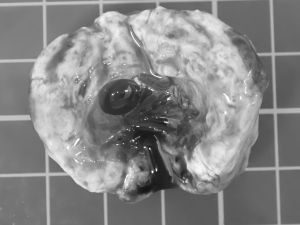

小さな体に負担がかからないよう慎重に麻酔をかけ、腫瘤を周囲の組織から丁寧に分離して摘出。

病理検査の結果、腫瘤は「組織球肉腫」という腫瘍でした。